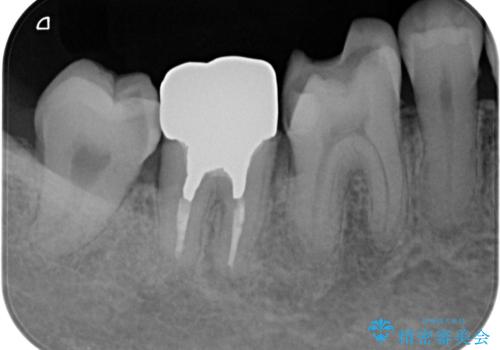

歯周ポケットの除去を併用したセラミック治療

適合や審美性に優れるセラミック治療を行う前に、歯周病の問題を歯周外科を行うことで解決し将来的に不安のないような口腔内環境を整備していきます。

- 110万円(ジルコニアクラウン×6・仮歯×6 歯周外科×2)費用は治療当時の料金となります

治療前に4-5mm程度あった歯周ポケットは全て2mm以内となり、非常に清掃性が高く、歯周病の再発しずらい環境に整えた上でのセラミック治療を実践することができました。